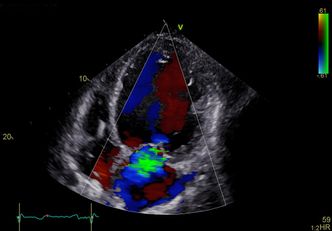

Fargekodingen for avstand, blant annet utviklet av GE største konkurrent, Phillips, gir kirurgen godt dybdebilde. Bildet kan snus og vendes og "lyssetting" endres for å få fram skygger og dybder.

Hjertekirurg Bijoy Khandheria ved Aurora St. Luke's Medical Center i Milwaukee, sier at det er som å se hjertet i "ekstrem 4D" med Vivid E95.

– Bildene er helt fantastiske. Det er som åpne brystkassen og se rett inn på hjertet som slår, sier han i en pressemelding.

Han sier at man kan se blodstrømmen og strømningsvirvlene rundt propper i arteriene. Det gir uvurderlig informasjon til kirurgene før operasjon.